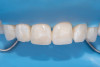

(27.) Final intraoral view after complete polymerization under glycerin gel, showing a seamless repair with invisible margins, making the fracture line undetectable.

Figure 27